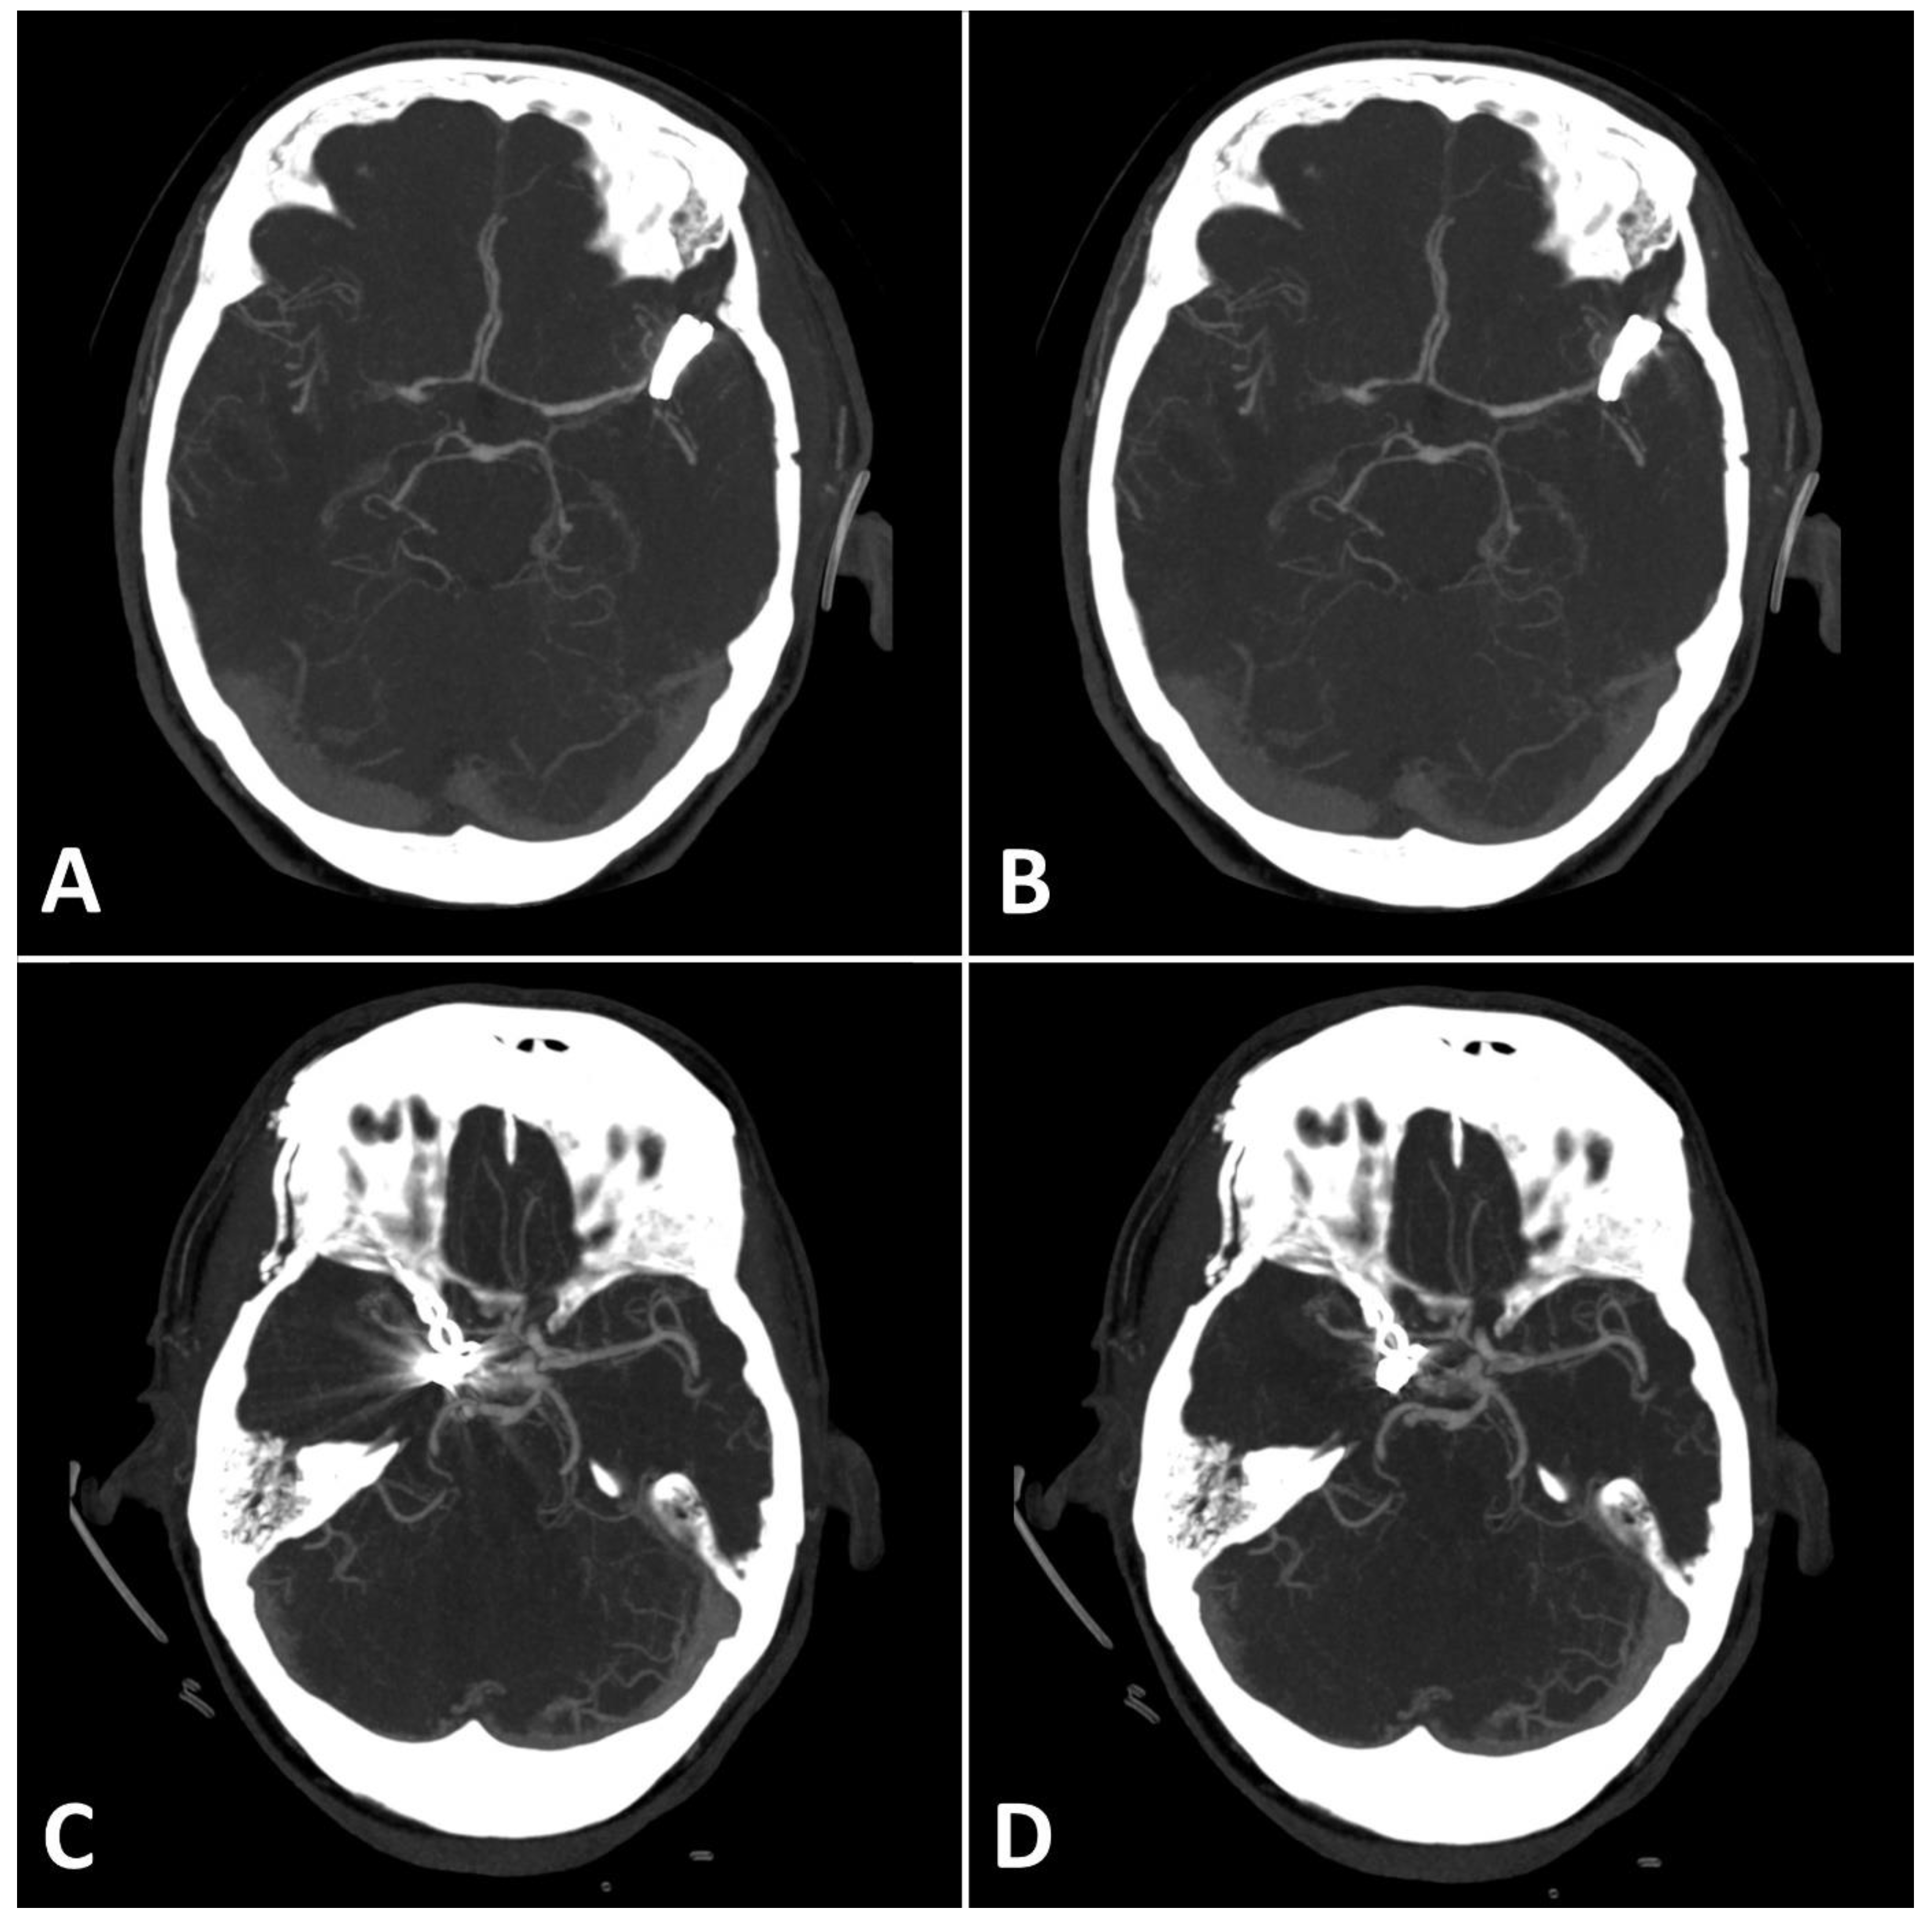

Figure 4.

(A,B): Exemplary follow up UHR-CT-angiography in axial plane without (A) and with SEMAR (B) of a 74-year-old female with an intracranial clip in the left middle cerebral artery. (C,D): Exemplary follow up UHR-CT-angiography in axial plane without (C) and with SEMAR (D) of a 63-year-old female with an intracranial clip in the right internal carotid artery. All images were reconstructed as MIP (Maximum Intensity Projection) with 12.5 mm slice thickness and demonstrate the effects of SEMAR on images with clip-artifacts.

MAI in images with clips was significantly lower in close vicinity (SEMAR: 26.5 ± 55 vs. standard: 113.7 ± 95.4; p = 0.036) and more distally from the clip (SEMAR: 23.6 ± 6.5 vs. standard: 29.3 ± 16.8; p = 0.007). Figure 4 demonstrates the effects of SEMAR on images with clip-artifacts.